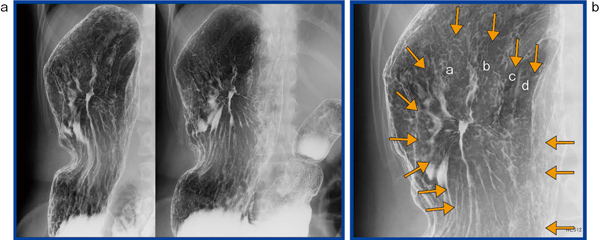

図1は,撮影中に技師が透視画像で微小がんに気づき,追加撮影を行った画像である。図1では,前庭部前壁に微小胃がんが認められる。びらんのようにも見えるが,棘状で外に広がるようなspicular formation cancerが明瞭に描出されている。

図1 X線検査の追加撮影により診断された |